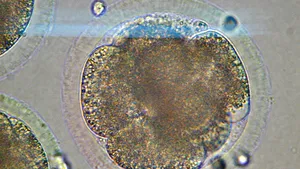

O nouă tehnologie de scanare a embrionilor poate detecta malformaţiile genetice

O nouă tehnologie de scanare a embrionilor, în vederea depistării malformaţiilor genetice, poate dubla şansele de succes ale unei fertilizări in vitro, potrivit cercetătorilor britanici, relatează BBC News Online. Această tehnologie a fost prezentată la o conferinţă pe tema fertilităţii, în SUA, iar cercetătorii britanici o susţin cu încredere.